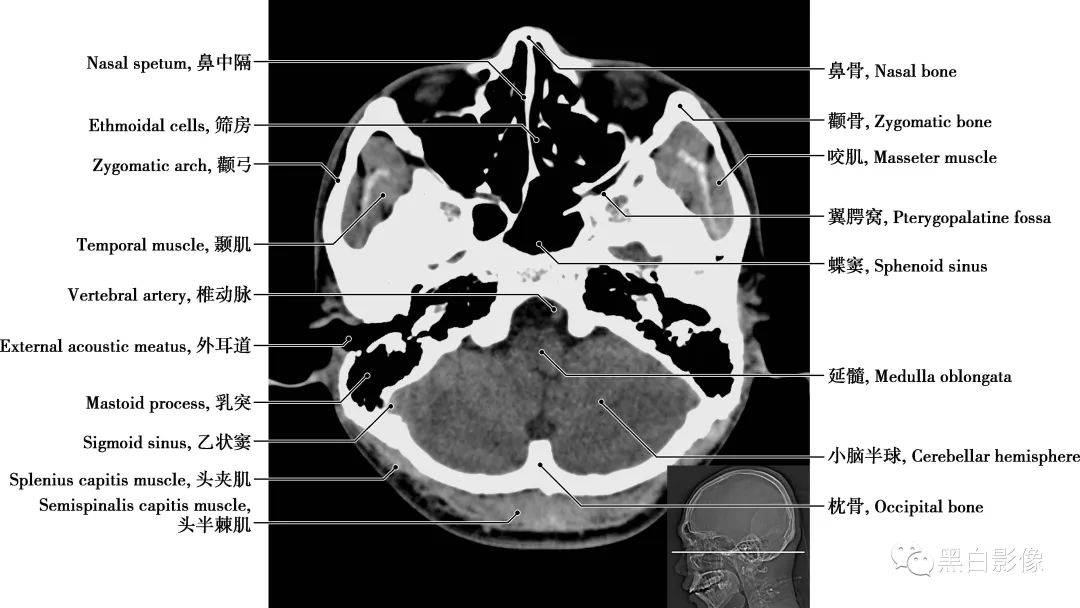

ct入门颅脑ct精美解剖详细标注

详细颅脑ct正常解剖图谱,带标注,值得收藏!